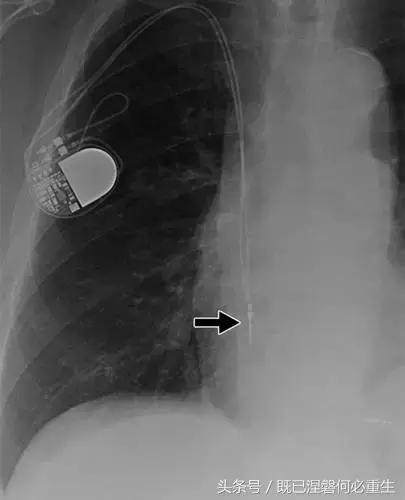

图。 6B 75岁的男性患有心房导线脱位。

B,Medtronic双腔起搏器的右心房导联(箭头)在正面(A)和侧面(B)图像上显示纯垂直路线。 铅在心房中自由浮动。 患者抱怨经常心悸,并且设备检查显示不能可靠地去极化心房。 心房导线修订(未示出)导致心悸消除。 心房导线的推荐放置位于右心耳,但右心房中的导联可充分发挥作用。 在任一位置正确固定到壁上的引线通常将显示一定程度的曲率。